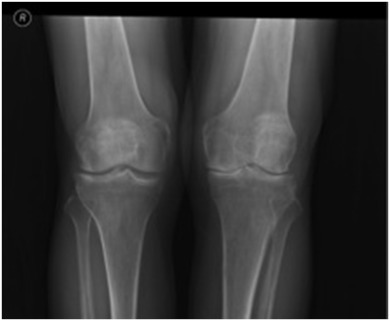

A 55-year-old male presented complaining of chronic knee pain that had worsened over the previous 3 years. This had been treated medically and with physiotherapy for the last year. The treatment included anti-inflammatory medications, two injections with viscosupplementation, and two intra-articular steroid injections, but resulted in no sustained improvement. On physical examination, the left knee was neutrally aligned. There was a mild effusion, with tenderness over the medial and lateral joint lines. The range of movement was from 0° of extension to 120° of flexion; extension was painless, while knee flexion was painful over the terminal 40°. There was no laxity of the collateral or cruciate ligaments. The distal neurovascular examination of the extremities was intact and symmetric. Radiographically, the left knee showed degenerative osteophytic changes and osteophytes in all compartments of both knees, with narrowing and sclerosis of the medial joint space (Fig. 1 ). The patient also had the darkly stained sclera and pinnae characteristic of ochronosis (Fig. 2 ).

Fig. 1

Fig. 1.

Preoperative radiographs showing osteoarthritic changes.